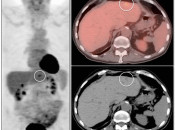

The normal liver demonstrates diffuse FDG uptake (typically greater than or equal to the spleen).

Many readers consider the uptake in the liver to represent the “background metabolic activity” for an exam.

For assessment of many lesions found in the body, the metabolic activity of the liver serves as the reference threshold by which to decide what is benign (uptake < liver) and what is malignant (uptake > liver).

Focal increased FDG uptake in the liver is always highly suspicious for malignancy. Very commonly, these malignant lesions may be poorly delineated on the co-registered CT images due to the lack of intravenous contrast administration.

Non-avid, low attenuation liver lesions are almost always benign (usually representing cysts, hemangiomas or fully treated malignant lesions), although some hepatocellular carcinomas can demonstrate only very mild metabolic activity.